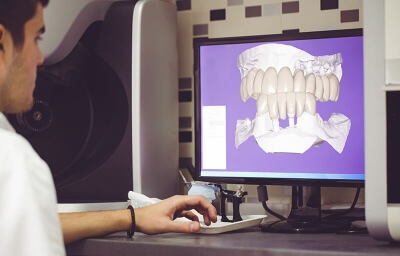

Кейс по лечению периимплантита на имплантате BICON

В данном кейсе автор при помощи Биоматрикса (мембрана) и Биоимплантат ГАП пошагово показывает, как спасти имплантат от развившегося периимплантита в следствии краевой резорбции.

Обратите внимание на обработку кости и самого имплантата от гранулята и произошедшей краевой резорбции.

Показан отдаленный результат (2 года) такого протокола лечения